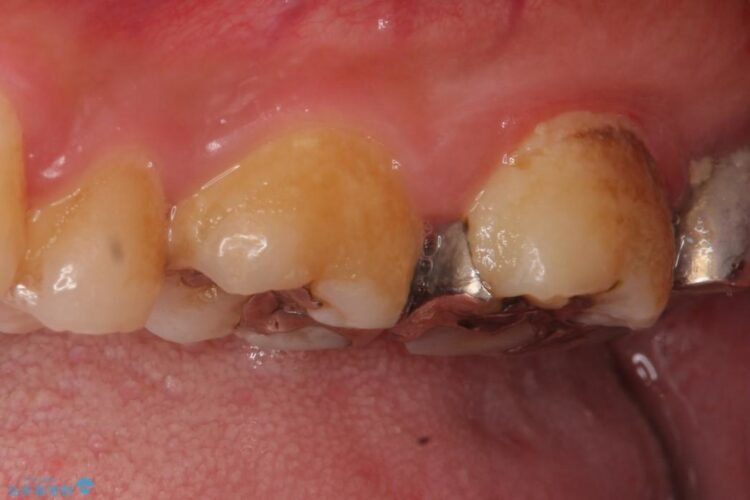

古い詰め物を外し、白く審美性の高いセラミックインレーにて再治療を行うこととしました。

今回は保険で治療してあった銀歯を審美性からセラミックインレーにて再度治療しました。

保険で治療した銀歯は、経年劣化で詰め物のふちが欠けたり、適合が悪くなり詰め物の下など目に見えない部分の虫歯の原因となることがあります。また、金属のため口にするものの熱の影響を受けやすく成分が溶けやすくなったり、変形してしまうことがあります。